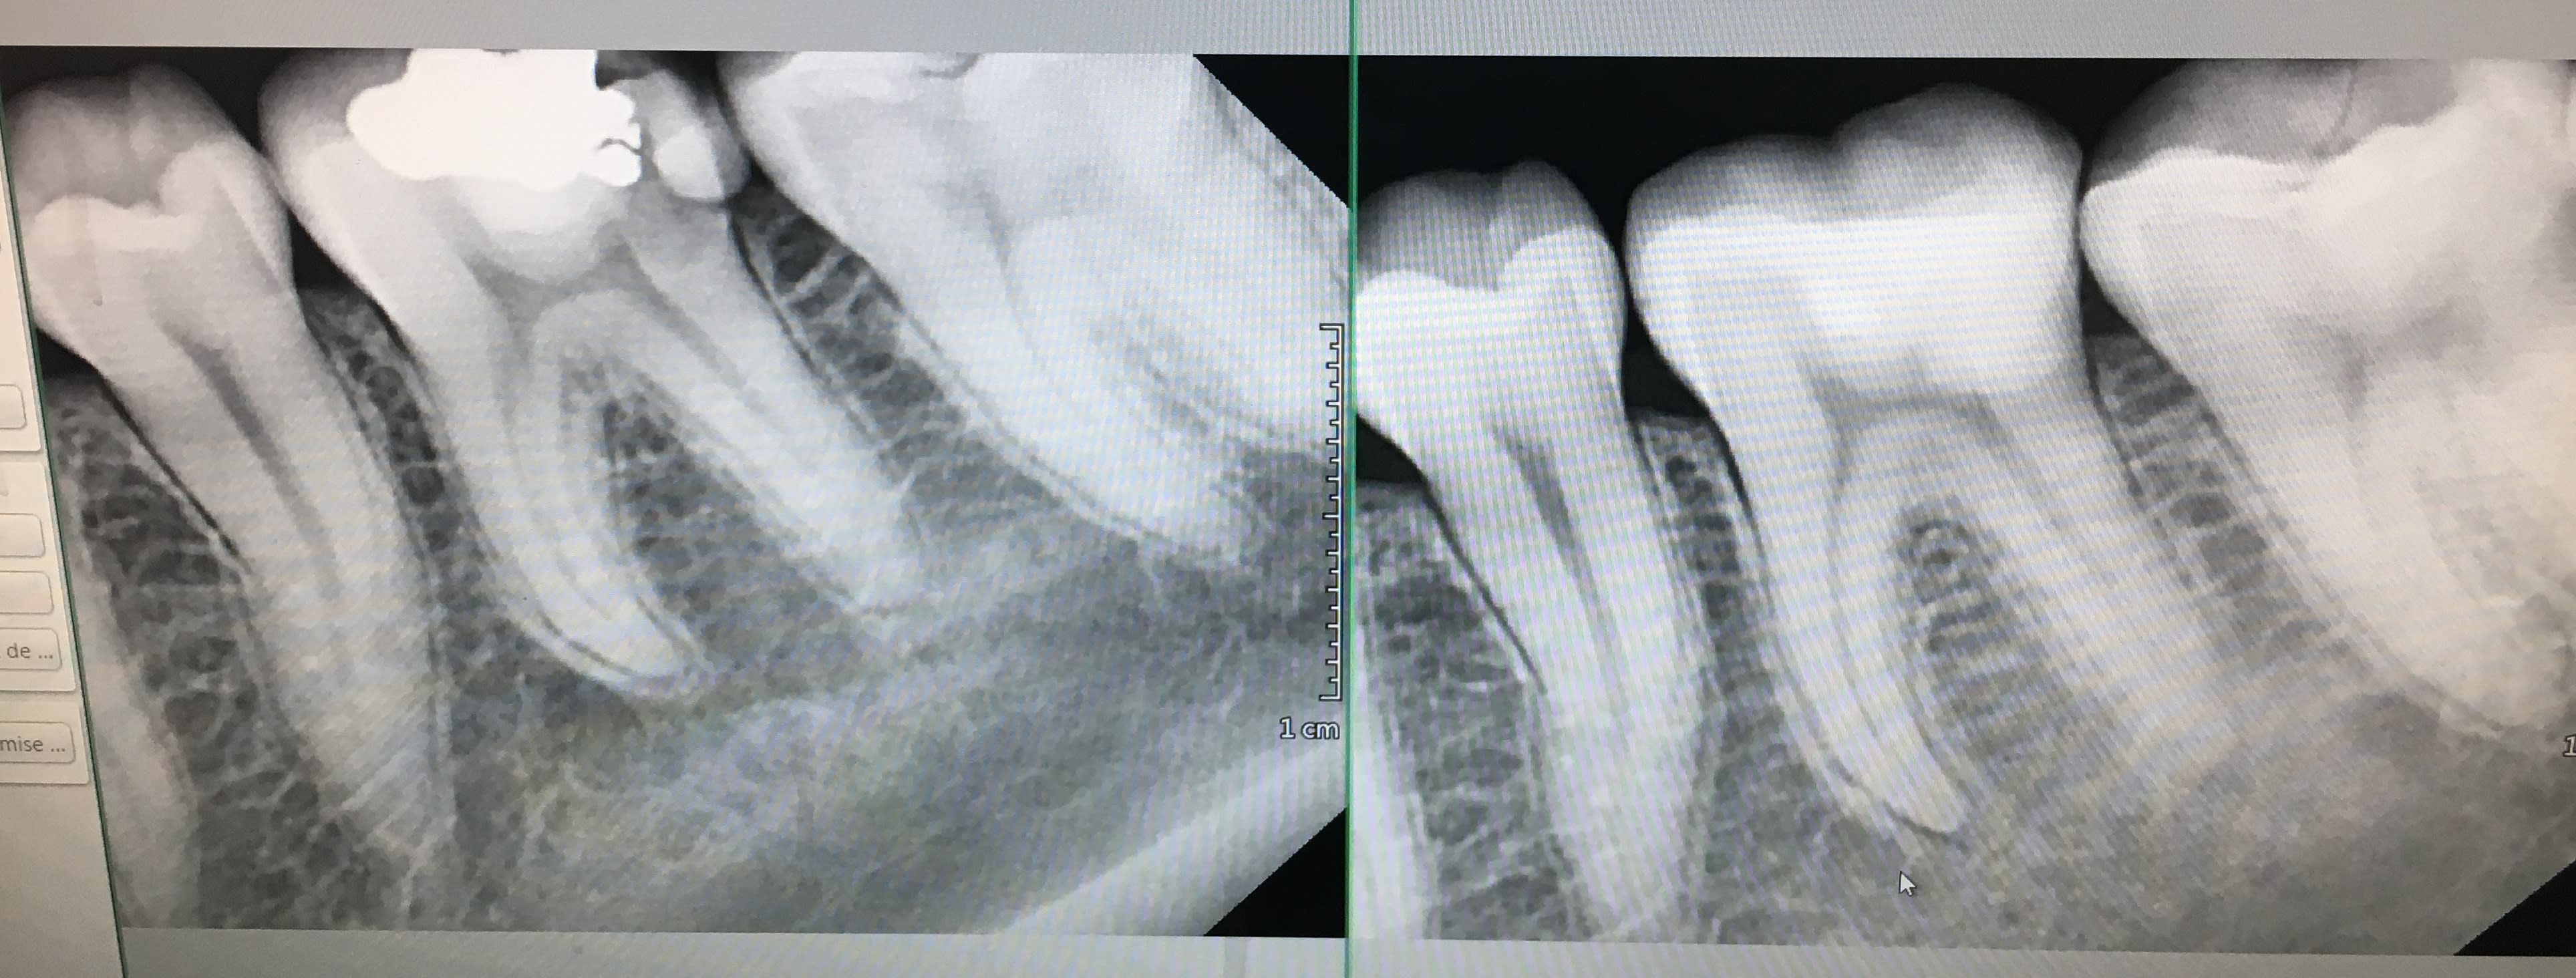

Elle avait une carie sur 36 vivante avec atteinte pulpaire sans symptomatologie.

J'ai donc déposél'amalgame présent, effectué un curetage carieux et obtenu mon hémostase très facilement au niveau de l'expo pulpaire qui était minime sur la corne distale, mis de la biodentine et après sa prise complète mis un CVI en temporisation.

Ma question concerne la suite, est-ce possible de laisser ma biodentine en place au niveau de la limite distale et de m'en servir comme remontée de marge pour le futur inlay (sorte de sandwich ouvert)?

voir la photo pour l’application d’un adhésif ou d’une colle sur la biodentine

Exactement t’as tout compris, la biodentine est n’est pas du tout lisse. Mettre un matériau irrégulier et non lisse en sous gingivale c’est pas ce qu’il y a de mieux pour éviter la rétention de plaque. Il y a qu’à Voir les obturations biodentine comme sur la photo, c’est totalement irrégulier, et t’auras beau fraiser et essayer de polir, ça restera une surface irrégulière . Après t’as septodont qui va te dire qu’on peut le faire. Et puis surtout le moindre coup de fraise ou d’insert et la biodentine s’effrite.